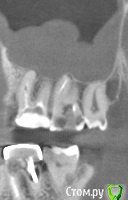

krokomot Опубликовано 24 февраля, 2015 Поделиться Опубликовано 24 февраля, 2015 Пациент решил подлечиться. Выявились проблемы с ранее лечеными по поводу осложненного кариеса зубами.Вот снимки зубов, конкретнее, зуба 2.7 содержащего во всех каналах инородные тела).(2.6 проходит ретритмент), но есть и КТ на нем в области фуркации 2.7 стенка менее 0,5 мм.Имеются признаки одонтогенного синусита (Ренгенологические) клинических нет. Вот вопрос кто-нибудь взлся бы детать ретритмент такого особенного зуба? Ссылка на комментарий

krokomot Опубликовано 26 февраля, 2015 Автор Поделиться Опубликовано 26 февраля, 2015 Дополняю снимками с КТ зуб с каналонаполнителями Ссылка на комментарий